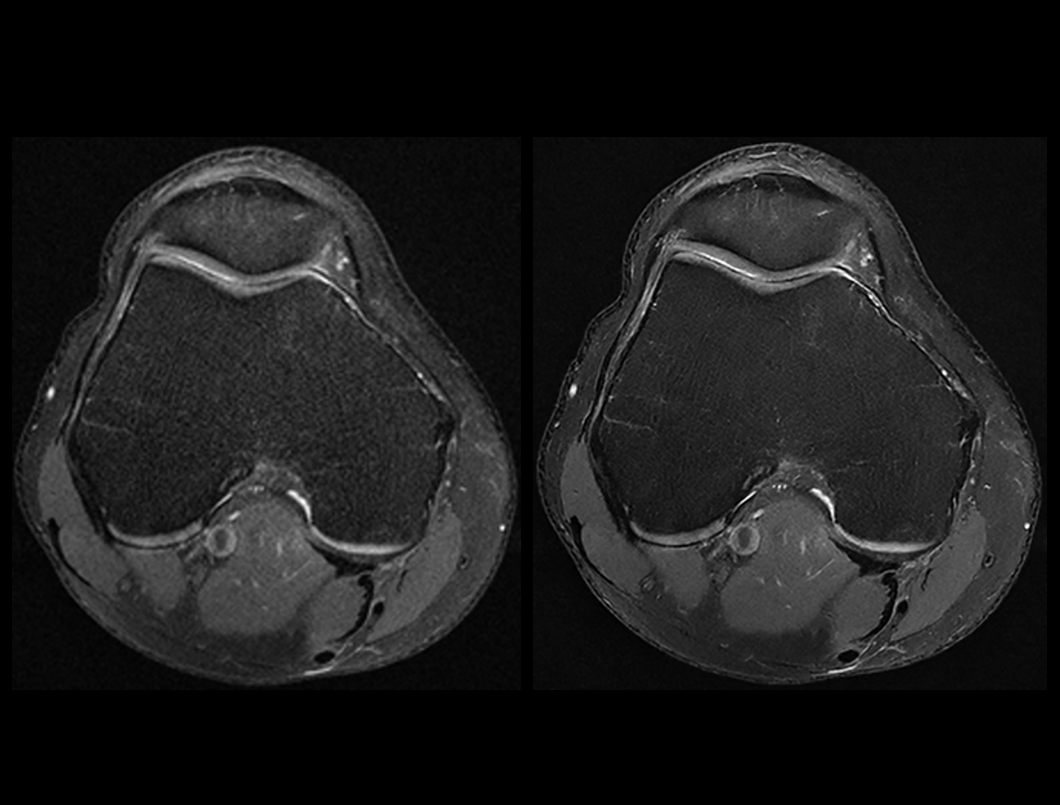

膝关节 PDW FS

常规成像 (2:32 min) vs. uAIFI DeepRecon™ (2:32 min)

0.35×0.35×3 mm3